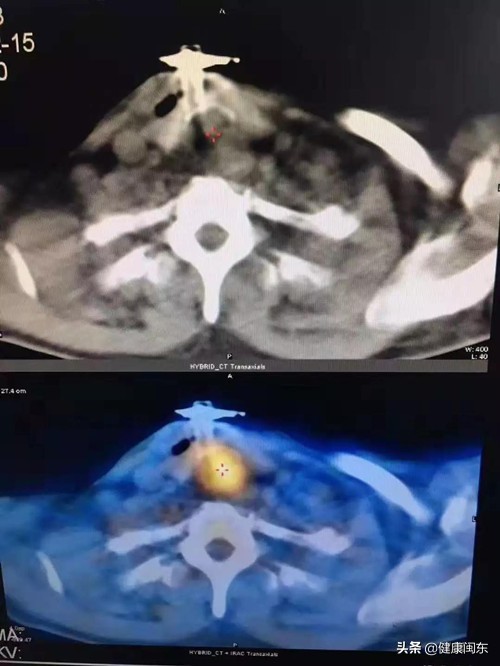

这下,老刘才慌了神,再次回到闽东医院检查,发现其咽喉肿瘤体积比两年前增大了许多,已经堵塞了大部分气管。

最终医生行全喉切除术,取出长度约5cm的咽喉肿瘤,从此老刘丧失了发音说话的功能。